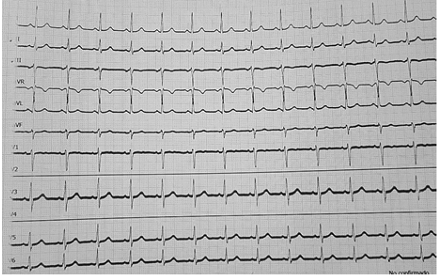

Aunado a la secuela de patología tuberculosa. Glicemia capilar de 97 mg/dl. Se solicitó interconsulta con UTI y laboratorios como hemograma, gasometría ( ver tabla 2), electrocardiograma de 12 derivaciones ( ver figura 1).

Se procedió al traslado de paciente a la Unidad de Terapia Intensiva, donde se complementó interconsultas con especialidades de neurología y cardiología, además de estudios como: tomografía de cráneo, radiografía de tórax, electroencefalograma (EEG) y estudio holter debido a que la paciente proviene de un lugar endémico de chagas.